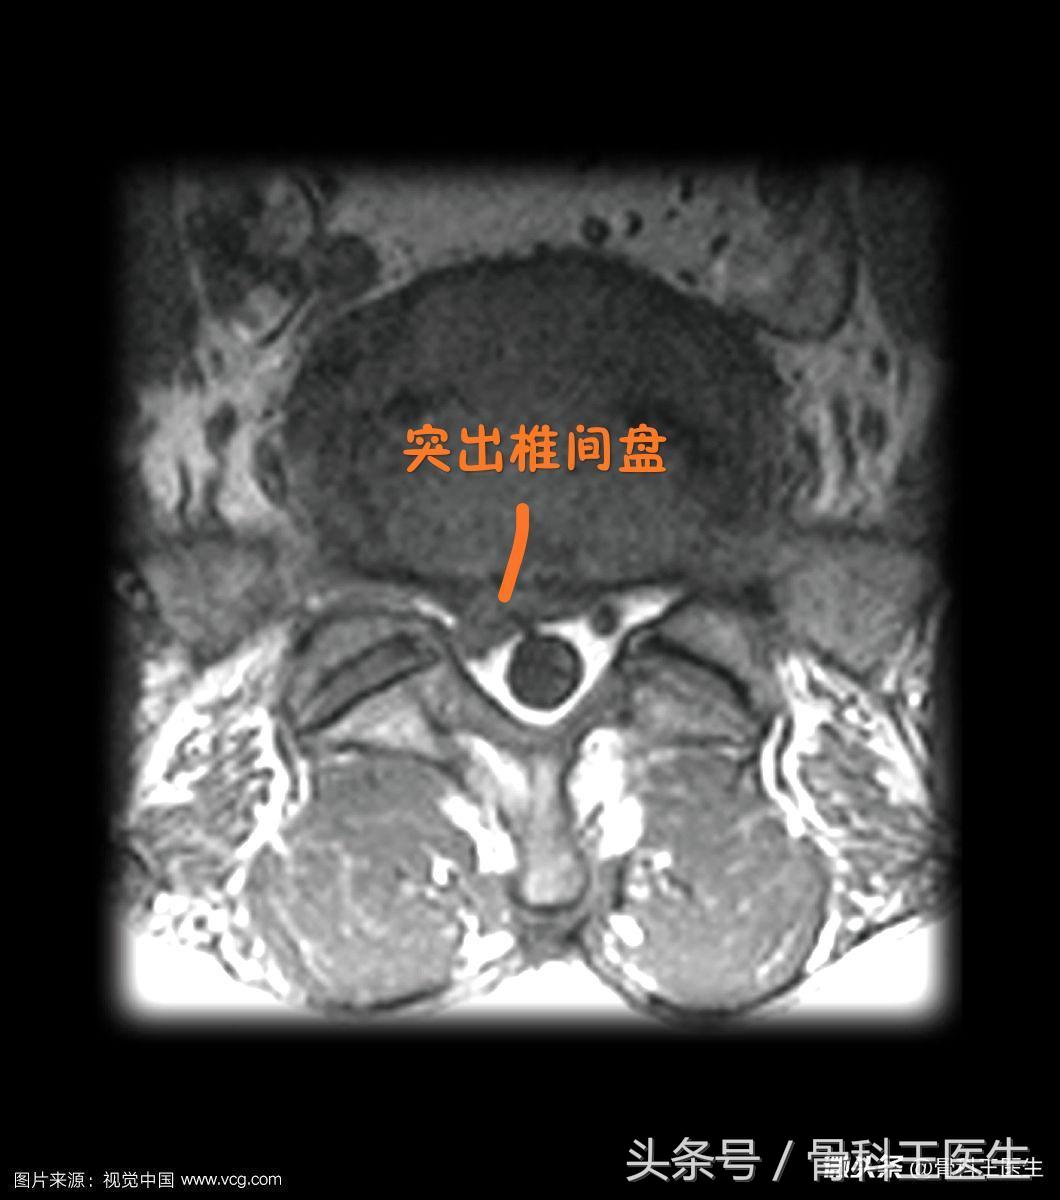

二、腰椎间盘突出怎么回事?

椎间盘=纤维环+髓核,纤维环正常是把髓核包在里面的,压力大了有点鼓出来,没破叫椎间盘膨出,包不住破了就叫突出。如果突出很大垂下来了,就叫脱出。最严重如果全部掉出来了,就叫做游离型了。